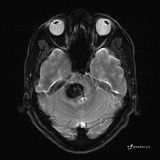

患者男,51岁。

简要病史:患者自述于1周前至某人民医院发现脑干肿瘤(具体不详),为求进一步诊断至我院就诊。

完善颅脑MRI平扫+增强,颅脑CT平扫:

T2: